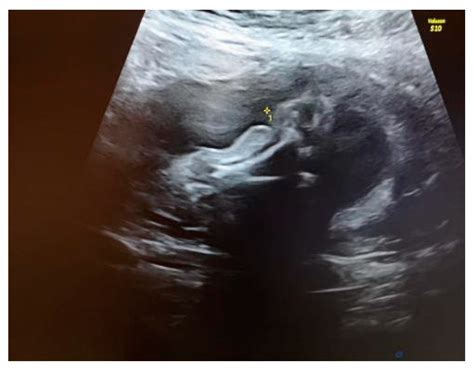

Early detection of Amniotic Band Syndrome through ultrasound is essential for timely intervention and better outcomes. *Amniotic Band Syndrome Ultrasound* involves detailed imaging of the fetus to identify the presence of fibrous bands and assess their impact on fetal development. This diagnostic tool is typically performed during routine prenatal check-ups, usually between 18 and 22 weeks of gestation.

• Imaging: A transducer is moved over the abdomen to capture images of the fetus. The ultrasound technician or radiologist will focus on areas where bands are likely to form, such as the limbs, head, and torso.

• Assessment: The images are analyzed to detect any signs of constriction, amputation, or other deformities caused by the bands.

• Detailed Anatomical Ultrasound: A more comprehensive ultrasound to evaluate the extent of the deformities.